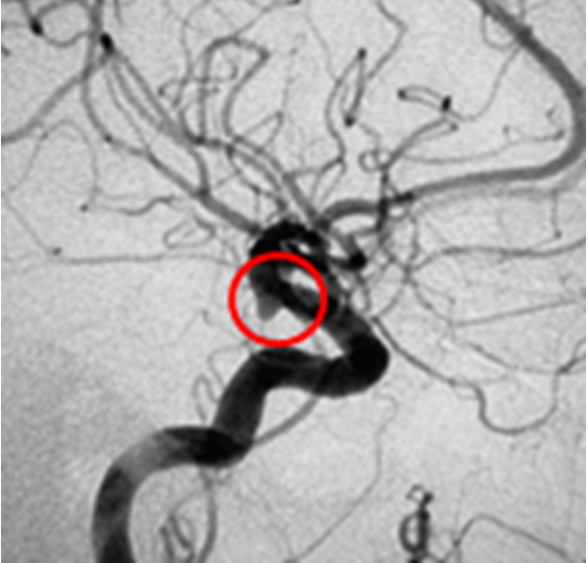

A 40-year-old male patient, with no previous diseases, was hospitalized due to subarachnoid hemorrhage, resulting from the rupture of an aneurysm at the level of the anterior communicating artery, diagnosed through conventional cerebral angiography, by catheterization (Figure 1). In addition to this aneurysm, an infundibular dilation of 6 mm in diameter was detected at the level of the right posterior communicating artery (Figure 2 and Figure 3). The radiologist suggested that it was a simple infundibular dilation, and the main focus of the radiological interpretation was to assess the characteristics of the anterior communicating artery aneurysm that had caused the subarachnoid hemorrhage.

Figure 2: Infundibular dilation at the level of the posterior communicating artery.

Share Image:

Figure 3: Typical conical infundibular dilation.